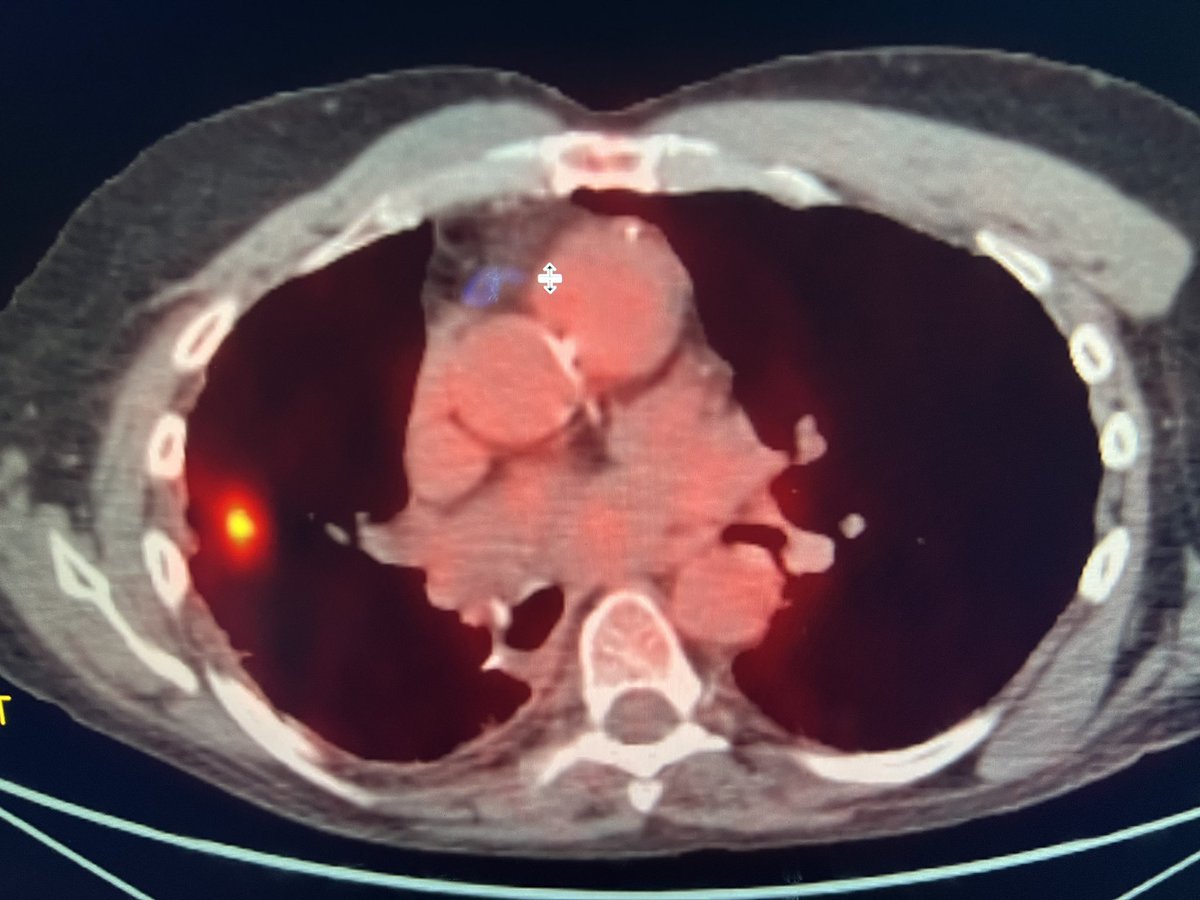

C-TRACT: a vital study for chronic blood clots. Visit bloodclotstudy.wustl.edu/c-tract/ to learn more. #patientcare #bloodclots #clinicalresearch #DVT